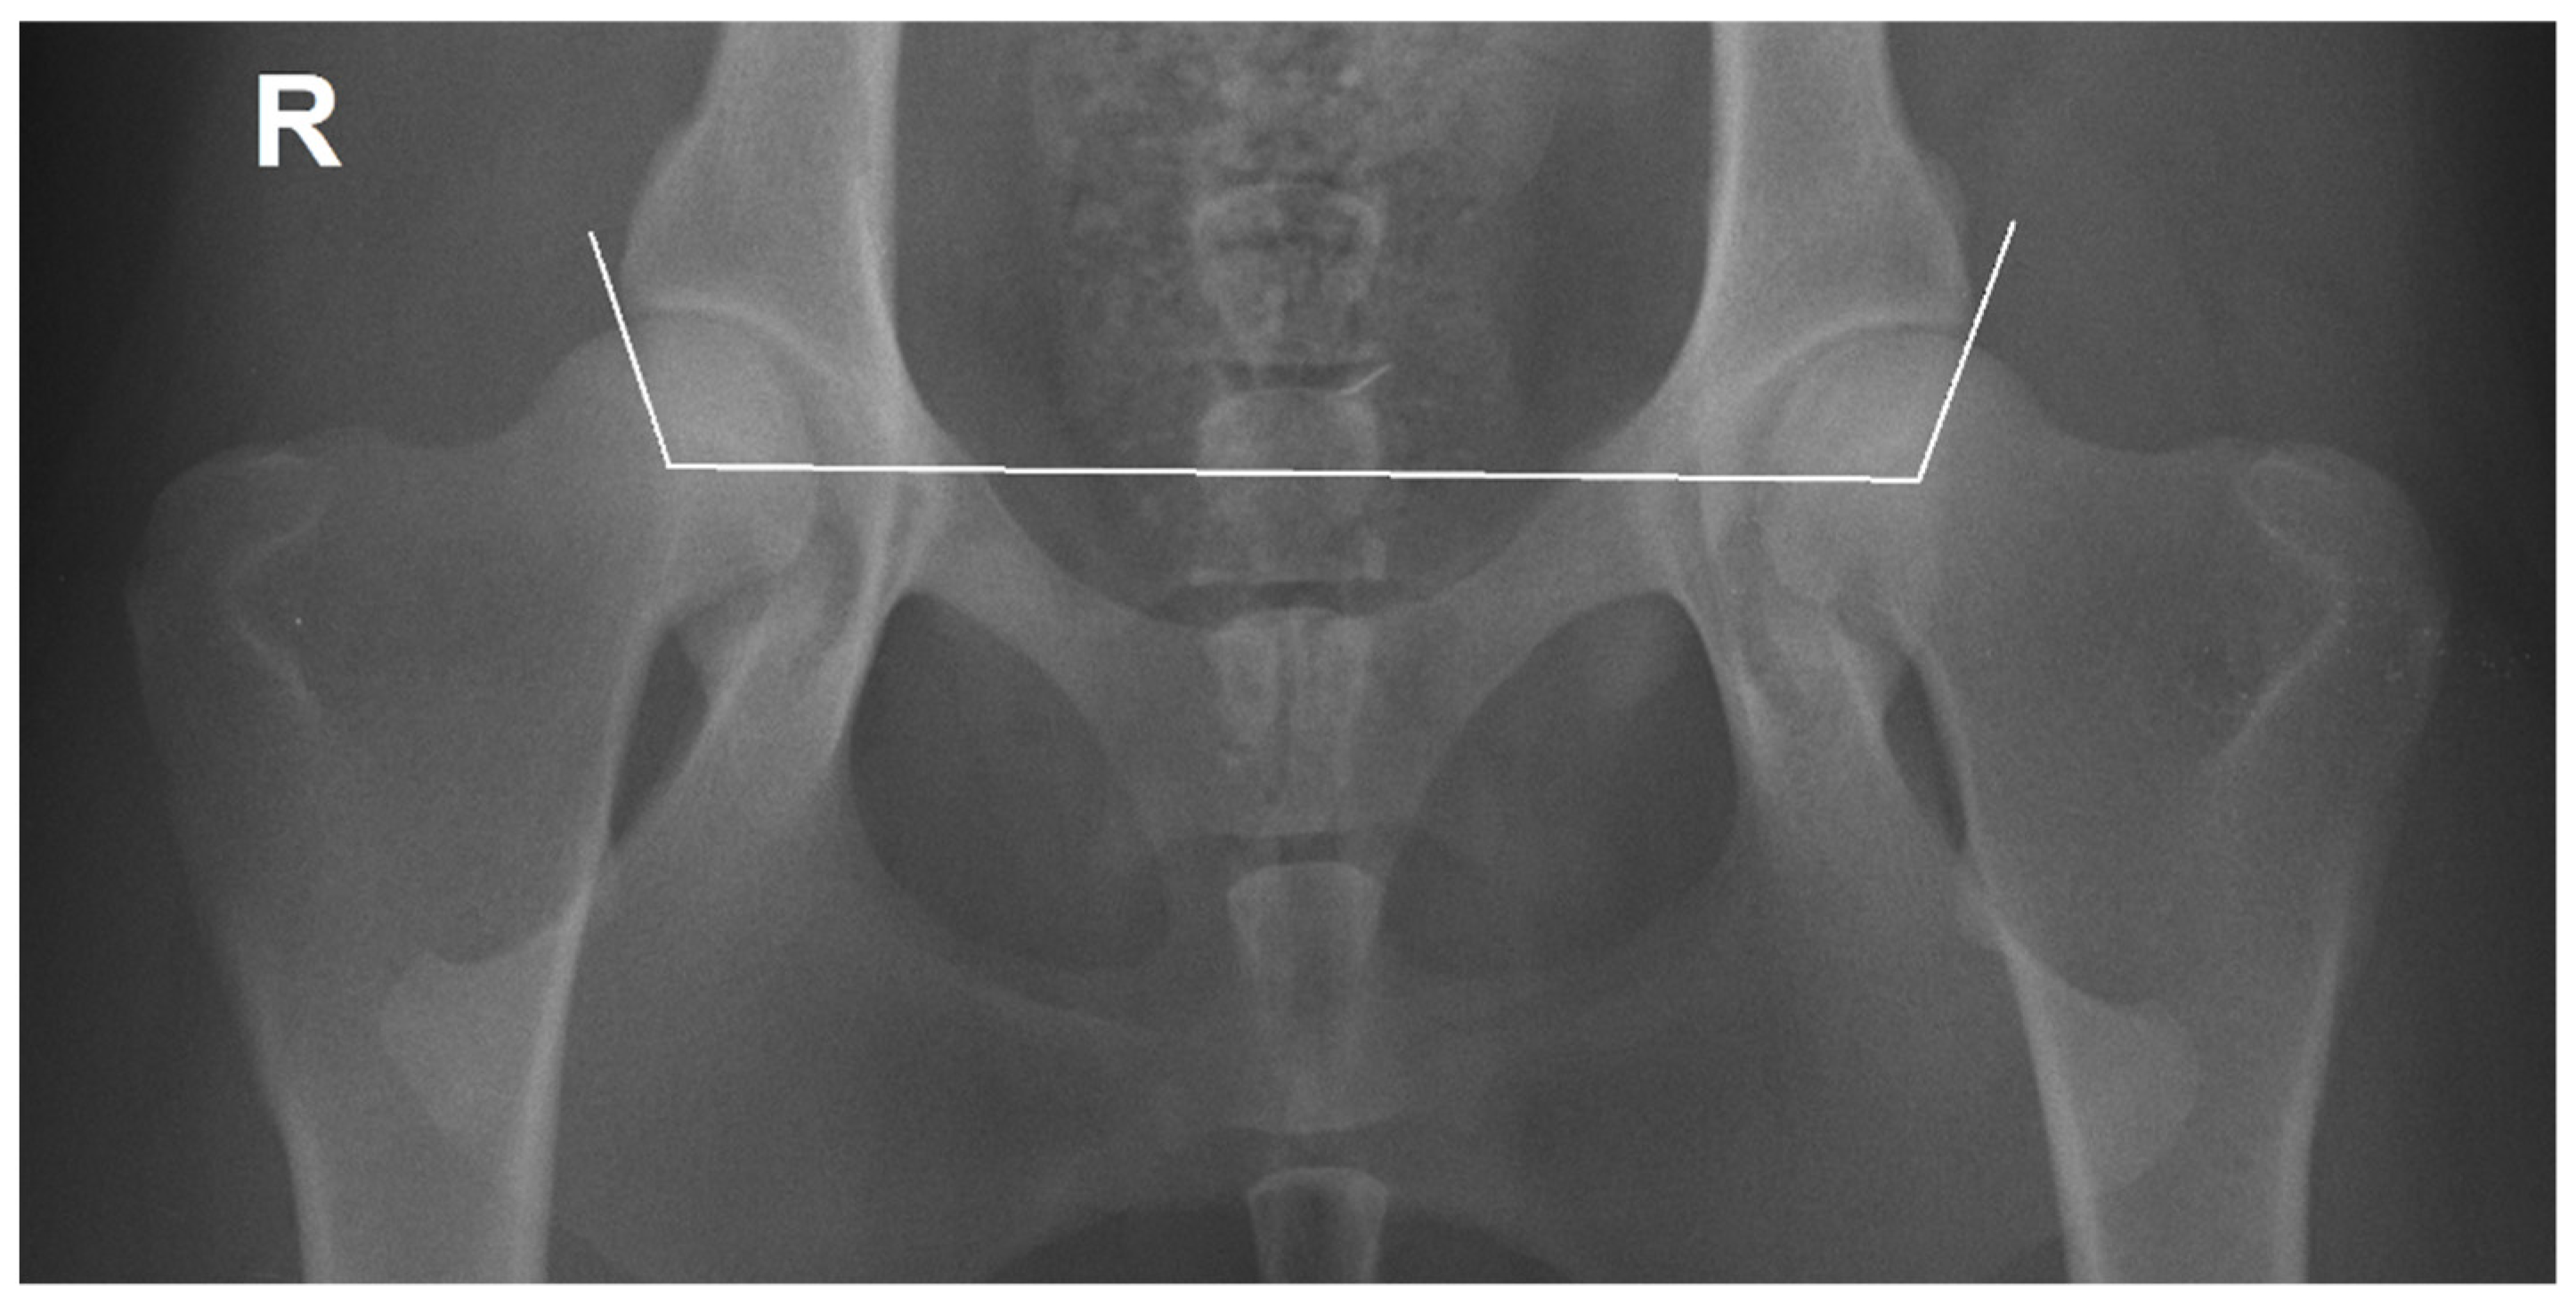

The 400 hip joints were scored into five categories for HD by M.G. using FCI criteria and a DICOM viewer and image analysis software (Dys4Vet version 1.1.0, accessed 12 June 2022). The criteria were as follows: A (no signs of HD—Norberg angle (NA) around 105° or more and excellent congruency); B (transitional or borderline hip joint—NA around 105° and mild incongruency); C (slight HD—NA around 100°, centre of femoral head outside of dorsal acetabular margin and moderate incongruency); D (moderate HD—NA around or greater than 90°, signs of osteoarthritis and obvious or considerable incongruency); E (severe HD—NA lower than 90°, signs of osteoarthritis and severe incongruency) [2,4]. The NA was measured between a line that joins the center of the femoral heads, and another line connecting each center of the femoral head with the cranial effective acetabular rim (Figure 1) [17]. Hip joints with NA around 105° or greater were considered normal. When the NA was around 100° or lower they were scored with different degrees of dysplasia [4].

Figure 1.

Ventrodorsal hip extended view of a female Transmontano Mastiff with no signs of hip dysplasia, right Norberg angle of 106° (left 110°) and an excellent congruency. The Norberg angle was calculated between the line joining the femoral centres of femoral heads and the other line connecting the centre of the femoral head and the cranial effective acetabular rim. R—right side.